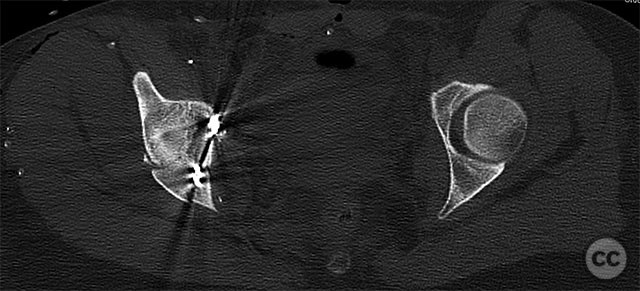

Clinical and radiological findings:  A 19-year-old female sustained a high-energy injury in a motor vehicle accident. Initial AP pelvic radiograph demonstrated a right-sided, displaced, comminuted associated both column acetabular fracture (AO/OTA 62C3), with a separate fracture fragment involving the greater sciatic notch (GSN). The right sacroiliac (SI) joint was incompletely disrupted. Surface rendered CT images confirmed the complex fracture morphology, including the separate GSN fragment and the SI-sacral injury, which rendered the typical posterior iliac fragment non-intact. Axial CT at the acetabular dome level revealed multiple displaced fragments and provided further detail regarding soft tissue involvement.